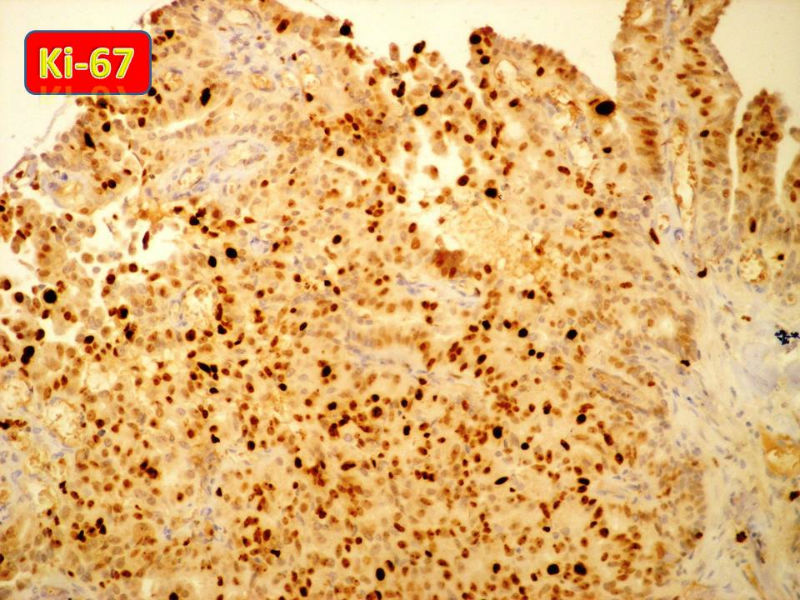

只能说是乳头状瘤

是不是导管内

乳头状瘤 and 导管内乳头状瘤 are the same; Benign lesion.

After you work up and you still cannot be sure it is benign , atypical or maignant lesion, you can call 乳头状lesion.

If this is excisonal case, you should figure out the nature of the papillary lesion.

我的意思就是提醒大家 在不是很确定的情况下 尽量少给自己套枷锁